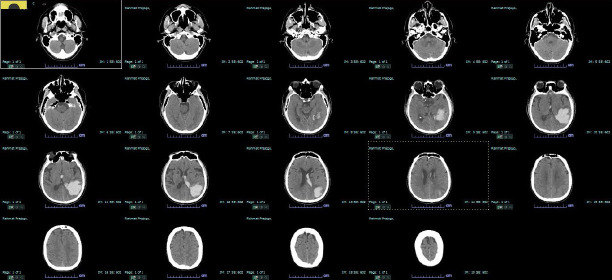

Optic aphasia is a rare neurological disorder that affects the visual-semantic ability of patients with normal vision and is caused by a lesion in the left occipital lobe. The signs and symptoms of optic aphasia are similar to those of associative visual agnosia, where patients have difficulty recognizing objects both in shape and function, resulting in challenges performing daily tasks. The transformation to optic aphasia or associative visual agnosia is closely related to the degree of damage to the corpus callosum, with some studies hypothetically suggesting that complete damage to the corpus callosum leads to optic aphasia, whereas incomplete damage causes associative visual agnosia. We present a case of a 60-year-old man with a history of intracerebral hemorrhage in the left occipitotemporoparietal lobe. The patient complained of intermittent episodes of painless, blurry vision. Upon examination, we observed that the patient was unable to read the Snellen chart, although he could draw the letter. Furthermore, we discovered that the patient had difficulty naming objects and instruments, even though he was able to express their shape and function through gestures and mimicry. The signs and symptoms of the patient, along with the result of the multi-slice non-contrast CT scan, suggest that he had optic aphasia rather than associative visual agnosia. A comprehensive neuropsychological and aphasia examination needs to be performed to further assess the condition of our patient and establish the diagnosis.

Abstract Image